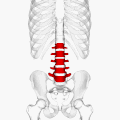

![]() Position of human lumbar vertebrae (shown in red). It consists of 5 bones, from the top down, L1, L2, L3, L4 and L5. | |

The lumbar vertebrae are located between the thoracic vertebrae and pelvis. They form the lower part of the back in humans, and the tail end of the back in quadrupeds. In humans, there are five lumbar vertebrae. The term is used to describe the anatomy of humans and quadrupeds, such as horses, pigs, or cattle. These bones are found in particular cuts of meat, including tenderloin or sirloin steak.

In human anatomy, the five vertebrae are between the rib cage and the pelvis. They are the largest segments of the vertebral column and are characterized by the absence of the foramen transversarium within the transverse process (since it is only found in the cervical region) and by the absence of facets on the sides of the body (as found only in the thoracic region). They are designated L1 to L5, starting at the top. The lumbar vertebrae help support the weight of the body, and permit movement.

Illustration highlighting lumbar spine.